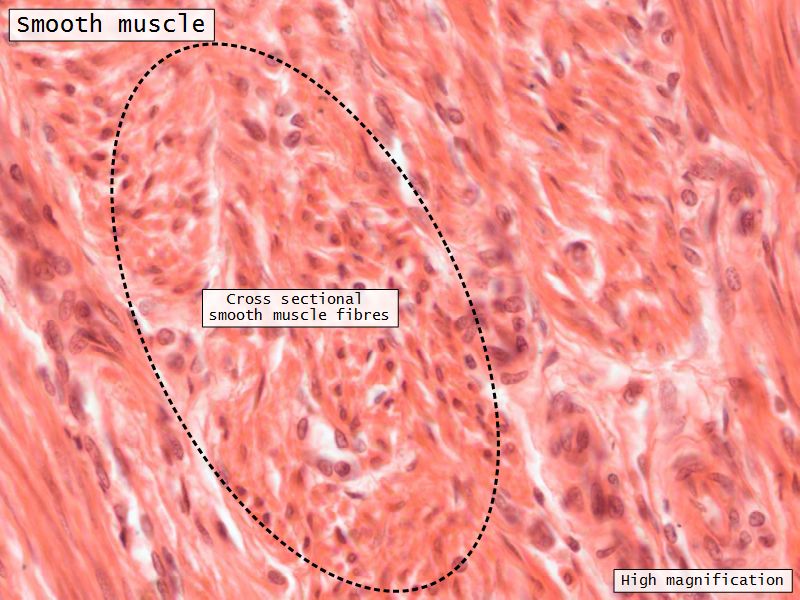

Myometrium

- 3 layers indistinct smooth

- Inner longitudinal/oblique

- Central circular

- Large blood vessels

- Stratum vasculare

- Outer longitudinal/oblique